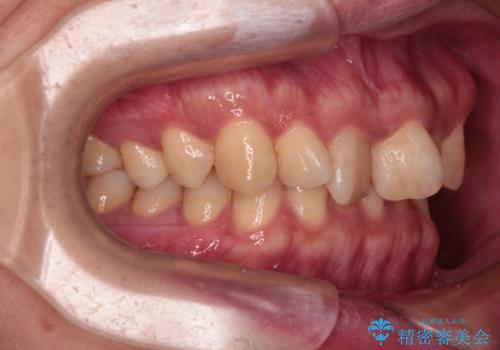

骨格的に上顎骨がやや前方にあり、それが原因で下顎前歯が隠れるほどのディープバイトになっている状態でした。

補助装置を用いて、上顎大臼歯を積極的に後方移動させながら、ディープバイトを改善していくこととしました。

強い咬合力に抵抗するため、上下ともに表側のワイヤー装置にて矯正治療を行うこととしました。